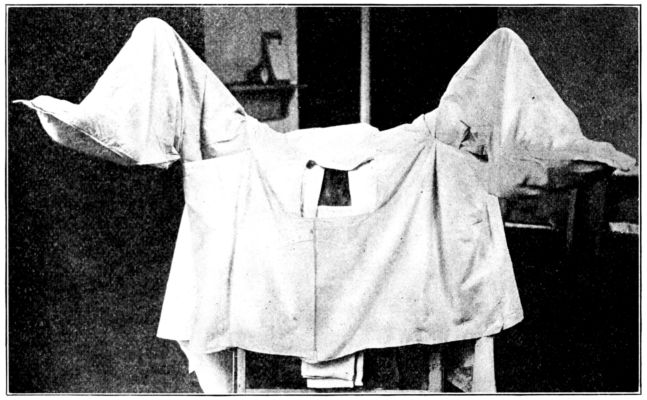

| 74. | Preparing patient for vaginal examination or delivery | 250 |

| 75. | Patient draped for vaginal examination | 251 |

| 82. | Patient draped with sterile dressings for delivery | 262 |